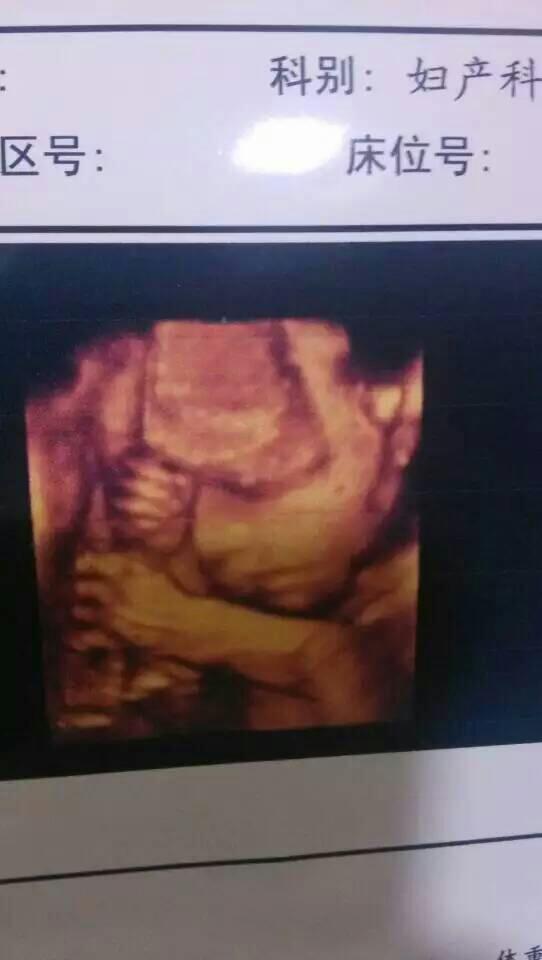

帮忙看看宝宝像谁多一点?

👃像爸爸